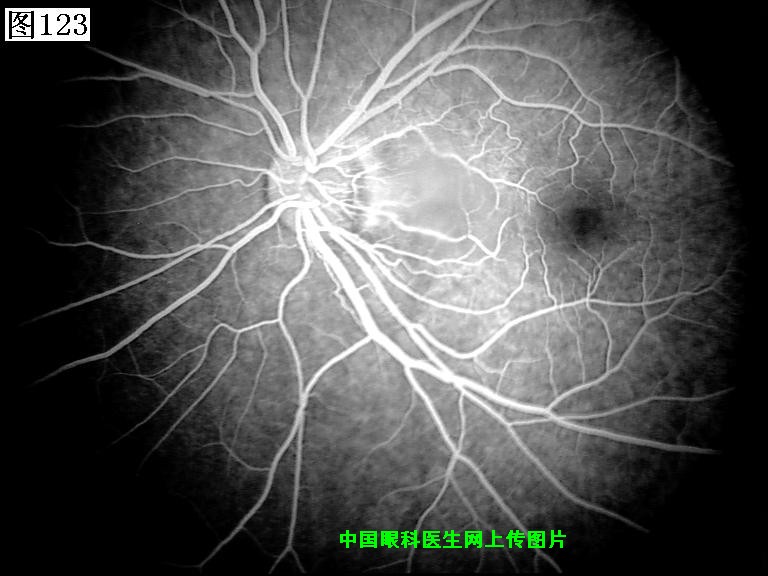

121 122 123 124